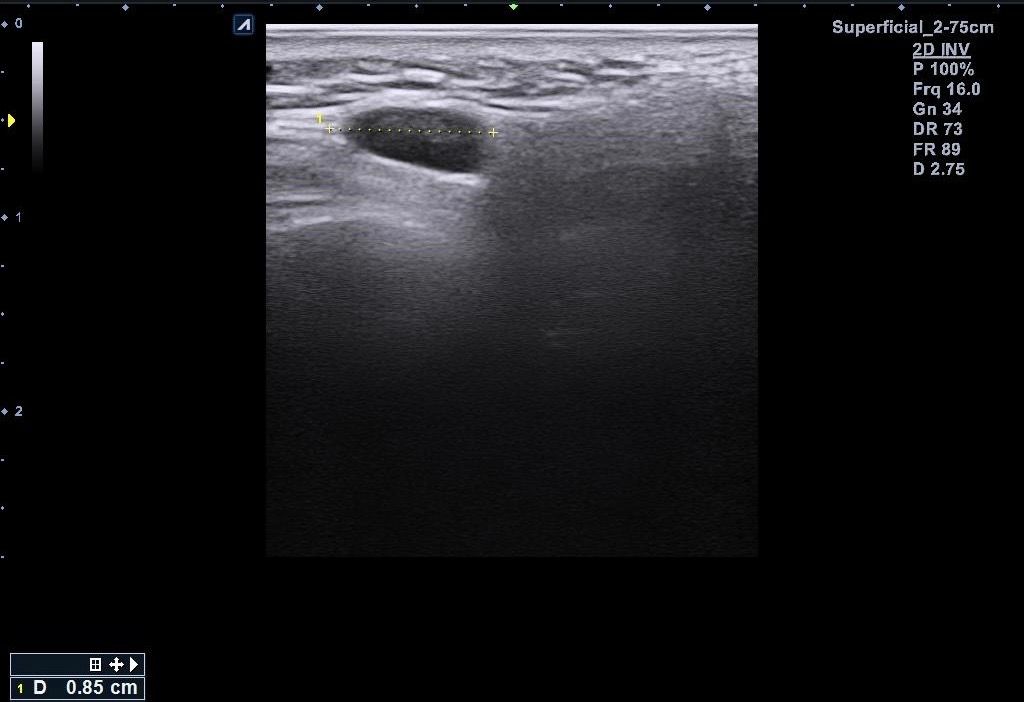

근데 병원에서 지방종이 아니라 임파선 같다고 일단 초음파 본다고 하시고 초음파를 봤는데 의사선생님이 귀 옆에 있는 임파선은 괜찮은데 아래에 있는 임파선이 초음파로 볼때 모양이랑 뭐가 조금 이상하다고 하시면서 대학병원가보라고 소견서를 써주셨습니다 (소견서랑 초음파사진 첨부할게요) 설명들을때 기억상으로는 1 2번째 초음파사진이 귀 아래였던 거 같아요

• 5번 째 사진